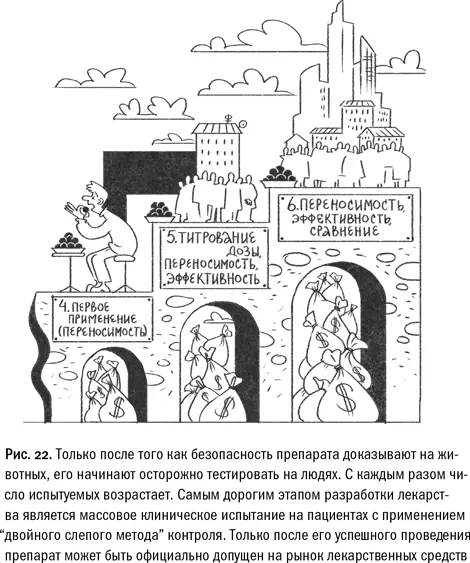

Фармацевтические корпорации ускоряют выход лекарства на рынок как могут. Частенько в жертву этой гонке приносится детальное исследование побочных эффектов, иногда эффективность препарата преувеличивается в недобросовестной рекламе. Это нехорошо, но выгодно и потому объяснимо. Но «закрытие» препарата, уже готового к массовому производству, влечет за собой гарантированные многомиллиардные убытки и «головы с плеч». На подобную меру компании идут лишь в исключительных случаях и никогда из соображений «вдруг препарат окажется слишком эффективным и другие наши лекарства станут не нужны», но всегда по причине всплывших побочных эффектов, чреватых огромными исками со стороны пациентов. Важно понимать, что оценить эффективность препарата заранее — до клинических испытаний — невозможно. Препарат, показавший впечатляющую эффективность на крысах, может оказаться совершенно неэффективным в отношении людей. Так что на этом этапе скрывать фармацевтической компании просто нечего, а после клинических испытаний скрыть их результаты почти нереально. Формат современного медицинского эксперимента с участием людей требует абсолютной прозрачности и информированного согласия от пациентов и врачей (иначе его результаты просто не будут признаны официальными инстанциями и деньги окажутся потрачены впустую). Количество людей, вовлеченных в процесс на данном этапе, исчисляется уже сотнями, а иногда и тысячами. Какая уж тут «абсолютная секретность»…

Так устроен союз фундаментальной науки и прикладной фармакологии в наши дни. Слабые стороны подобной системы видны, что называется, невооруженным глазом. Запредельно высокая стоимость клинических испытаний оборачивается дороговизной новых онкопрепаратов, а стремление к публикации «любой ценой» приводит к тому, что ученые самокритично называют «низкой воспроизводимостью» целого ряда опубликованных научных результатов. Все же одного у нее не отнять — эта система исключает возможность сокрытия важной научной информации (во всяком случае, в таких конкурентных областях, как молекулярная онкология). Тайное в ней неизменно становится явным.

ФАКТ:самым известным случаем отзыва с рынка уже одобренного медицинского препарата стала история «Талидомида» — снотворного, совершенно безопасного для лабораторных животных, но обнаружившего тератогенный эффект у человека. Женщины, принимавшие этот препарат во время беременности, рожали детей с выраженными уродствами, например без рук. Талидомидовая трагедия, в результате которой в мире в период с 1956 по 1962 год родилось около 10 000 детей с врожденными уродствами, заставила многие страны пересмотреть существующую практику лицензирования лекарственных средств и ужесточить требования к клиническим испытаниям препаратов. Фармацевтическая компания была обязана выплатить значительные денежные компенсации семьям пострадавших детей, но иски в ее адрес (уже от самих выросших жертв) продолжают поступать до сих пор.

ФАКТ:самым известным случаем отзыва с рынка уже одобренного медицинского препарата стала история «Талидомида» — снотворного, совершенно безопасного для лабораторных животных, но обнаружившего тератогенный эффект у человека. Женщины, принимавшие этот препарат во время беременности, рожали детей с выраженными уродствами, например без рук. Талидомидовая трагедия, в результате которой в мире в период с 1956 по 1962 год родилось около 10 000 детей с врожденными уродствами, заставила многие страны пересмотреть существующую практику лицензирования лекарственных средств и ужесточить требования к клиническим испытаниям препаратов. Фармацевтическая компания была обязана выплатить значительные денежные компенсации семьям пострадавших детей, но иски в ее адрес (уже от самих выросших жертв) продолжают поступать до сих пор.